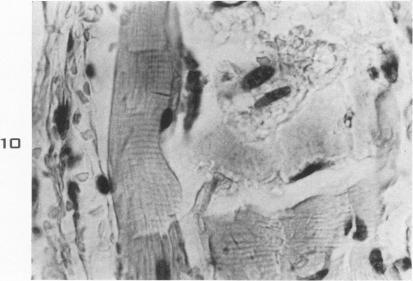

Lesions of skeletal muscle in leptospirosis; review of reports and an experimental study.

Am J Pathol. 1955 May-Jun;31(3):501-19.